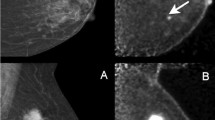

DBT is uniquely sensitive in the detection of subtle architectural distortion (a potential presentation of malignancy), which is in part responsible for its improved cancer detection rates. However, architectural distortion can also be due to non-malignant causes, most notably post-surgical changes or complex sclerosing lesions (i.e., radial scars). As noted previously, Lång et al. attributed their increased recall rate with DBT to the increased sensitivity for radial scars and post-operative scars [26•]. Partyka et al. have suggested that DBT-detected architectural distortion in the absence of a sonographic correlate has a higher likelihood of benignity [53], though others have disagreed. Freer et al., in their study assessing feasibility and accuracy of DBT-guided needle localization, reported that DBT-detected suspicious architectural distortion that is mammographically or sonographically occult has a 47% positive predictive value for malignancy [54]. Thus, at present, most sites agree that any architectural distortion that is visible solely with DBT should undergo DBT-guided biopsy (Fig. 1).

Fifty-year-old female with a history of left breast conservation therapy (lumpectomy and radiation) for invasive ductal carcinoma 9 years ago presents for annual screening mammogram. a 2D FFDM image reveals heterogeneously dense parenchyma, with several rim-calcified cysts (short arrow). b DBT plane reveals architectural distortion (long arrow), which is more apparent on magnification (c). No ultrasound correlate was identified. The patient underwent DBT-guided core biopsy, revealing invasive lobular carcinoma